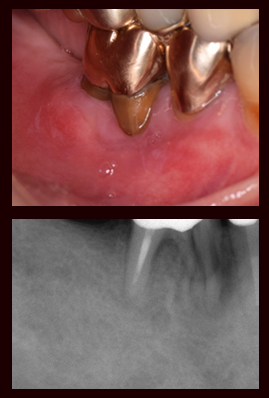

術後1年

固定された歯は術後少しずつ回復し、炎症や腫れも引いていきます。その後患者さんからも違和感なく食事ができると報告をいただいています。

治療前

この患者さんは他医院にて治療中の歯が割れたとのことで来院されました。歯肉の炎症が多くありませんが、レントゲン画像より上顎左側第一小臼歯が破折していました。

抜歯した歯

術後3か月

術後3か月経過したレントゲンでは、周りの骨が回復してきています。患者さんも何の違和感もなく食べれているとのことでした。